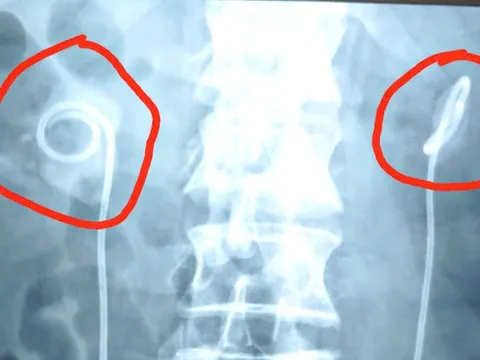

Ngỡ ngàng phát hiện người phụ nữ 32 tuổi có đến 19 khối u xơ trong tử cung

Mới đây, các bác sĩ Bệnh viện Việt Nam - Thụy Điển Uông Bí (Quảng Ninh) đã phẫu thuật thành công, bóc tách 19 khối u xơ tử cung cho một nữ bệnh nhân 32 tuổi (ở phường Đông Triều - Quảng Ninh).